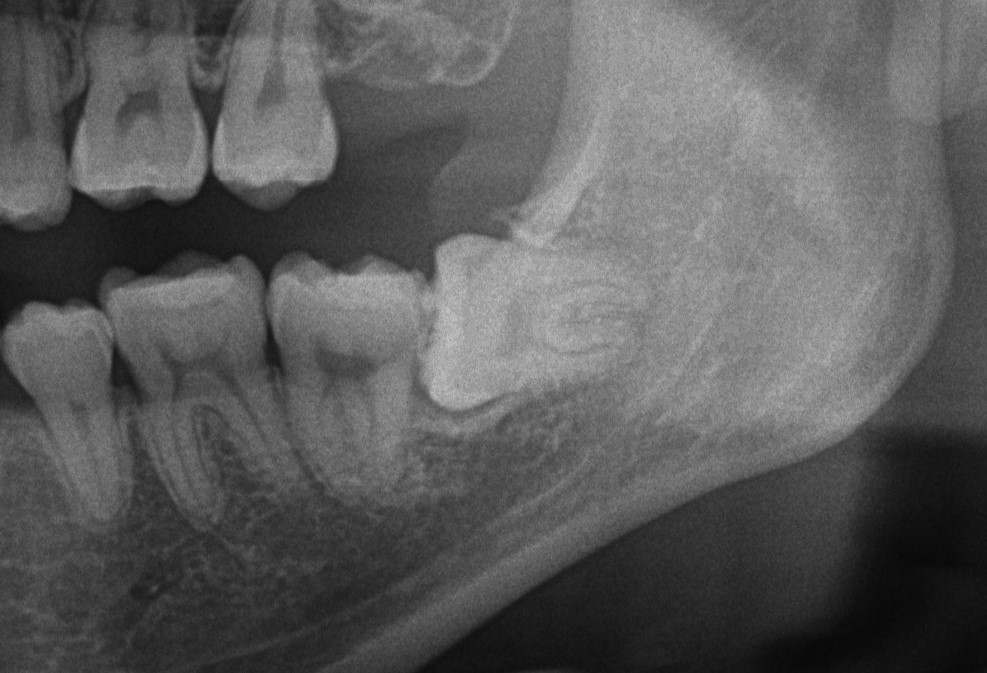

埋まっている親知らずは抜く必要があるのか?

「埋まっている親知らずは抜く必要があるのか?」という疑問をおもちの方がいるのではないでしょうか。実は完全に埋まっている親知らずでも、抜歯が必要になる場合があるのです。 今回は、抜いたほうがいい親知らずの特徴や、埋まってい […]

親知らずいる?いらない? Dr.三宮

人の歯は母親のお腹の中、あるいは生まれて間もない時期に作られ、決まった時期に生えてきます。 親知らずは退化傾向にある歯で大人になっても生えてこない場合があります。 また生えてきた場合でも顎の中に埋もれていたり、傾いたまま […]